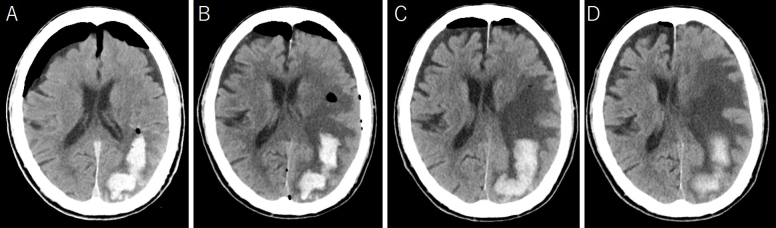

Porencephalic cysts are very rare in adults. Herein, we present a case of an 88-year-old man with a symptomatic expanding porencephalic cyst after intracerebral hematoma evacuation. He was admitted because of disturbed consciousness and right hemiparesis. A computed tomography (CT) showed a large subcortical hematoma in the left parietal lobe. Hematoma evacuation was performed, his consciousness level improved but gradually deteriorated. Follow-up CT revealed a new cystic lesion with perifocal edema at the hematoma site, with progressive expansion of the cyst. Cyst drainage and -peritoneal shunt placement were performed on postoperative day 14; consequently, his symptoms improved. Considerably, a porencephalic cyst have developed because the cerebrospinal fluid flowed into the closed hematoma cavity from the ventricle owing to the osmotic pressure difference between the ventricle and the hematoma cavity.